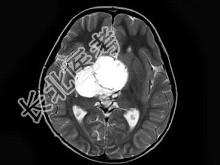

- 单项选择题女,51岁, 视力下降伴左侧面部麻木1个月,MRI检查如图所示, 应考虑为 ( )